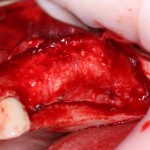

На фотографии ниже нам повезло — вы заметили перфорацию в ходе подготовки лунки под имплантат и приняли меры по ее устранению:

Однако, так везет далеко не всегда. Именно поэтому метод закрытого синуслифтинга имеет ряд ограничений: